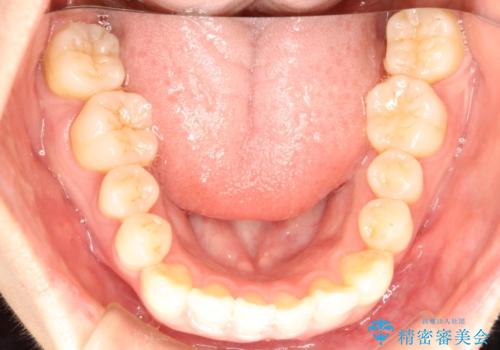

インビザラインで八重歯の矯正

- 八重歯を治したいとのことで、来院されました。

インビザラインにて、上顎の歯と歯の間をわずかに削り、並べる計画としました。

使用時間を守っていただけたので、比較的スムーズに矯正を終了することができました。